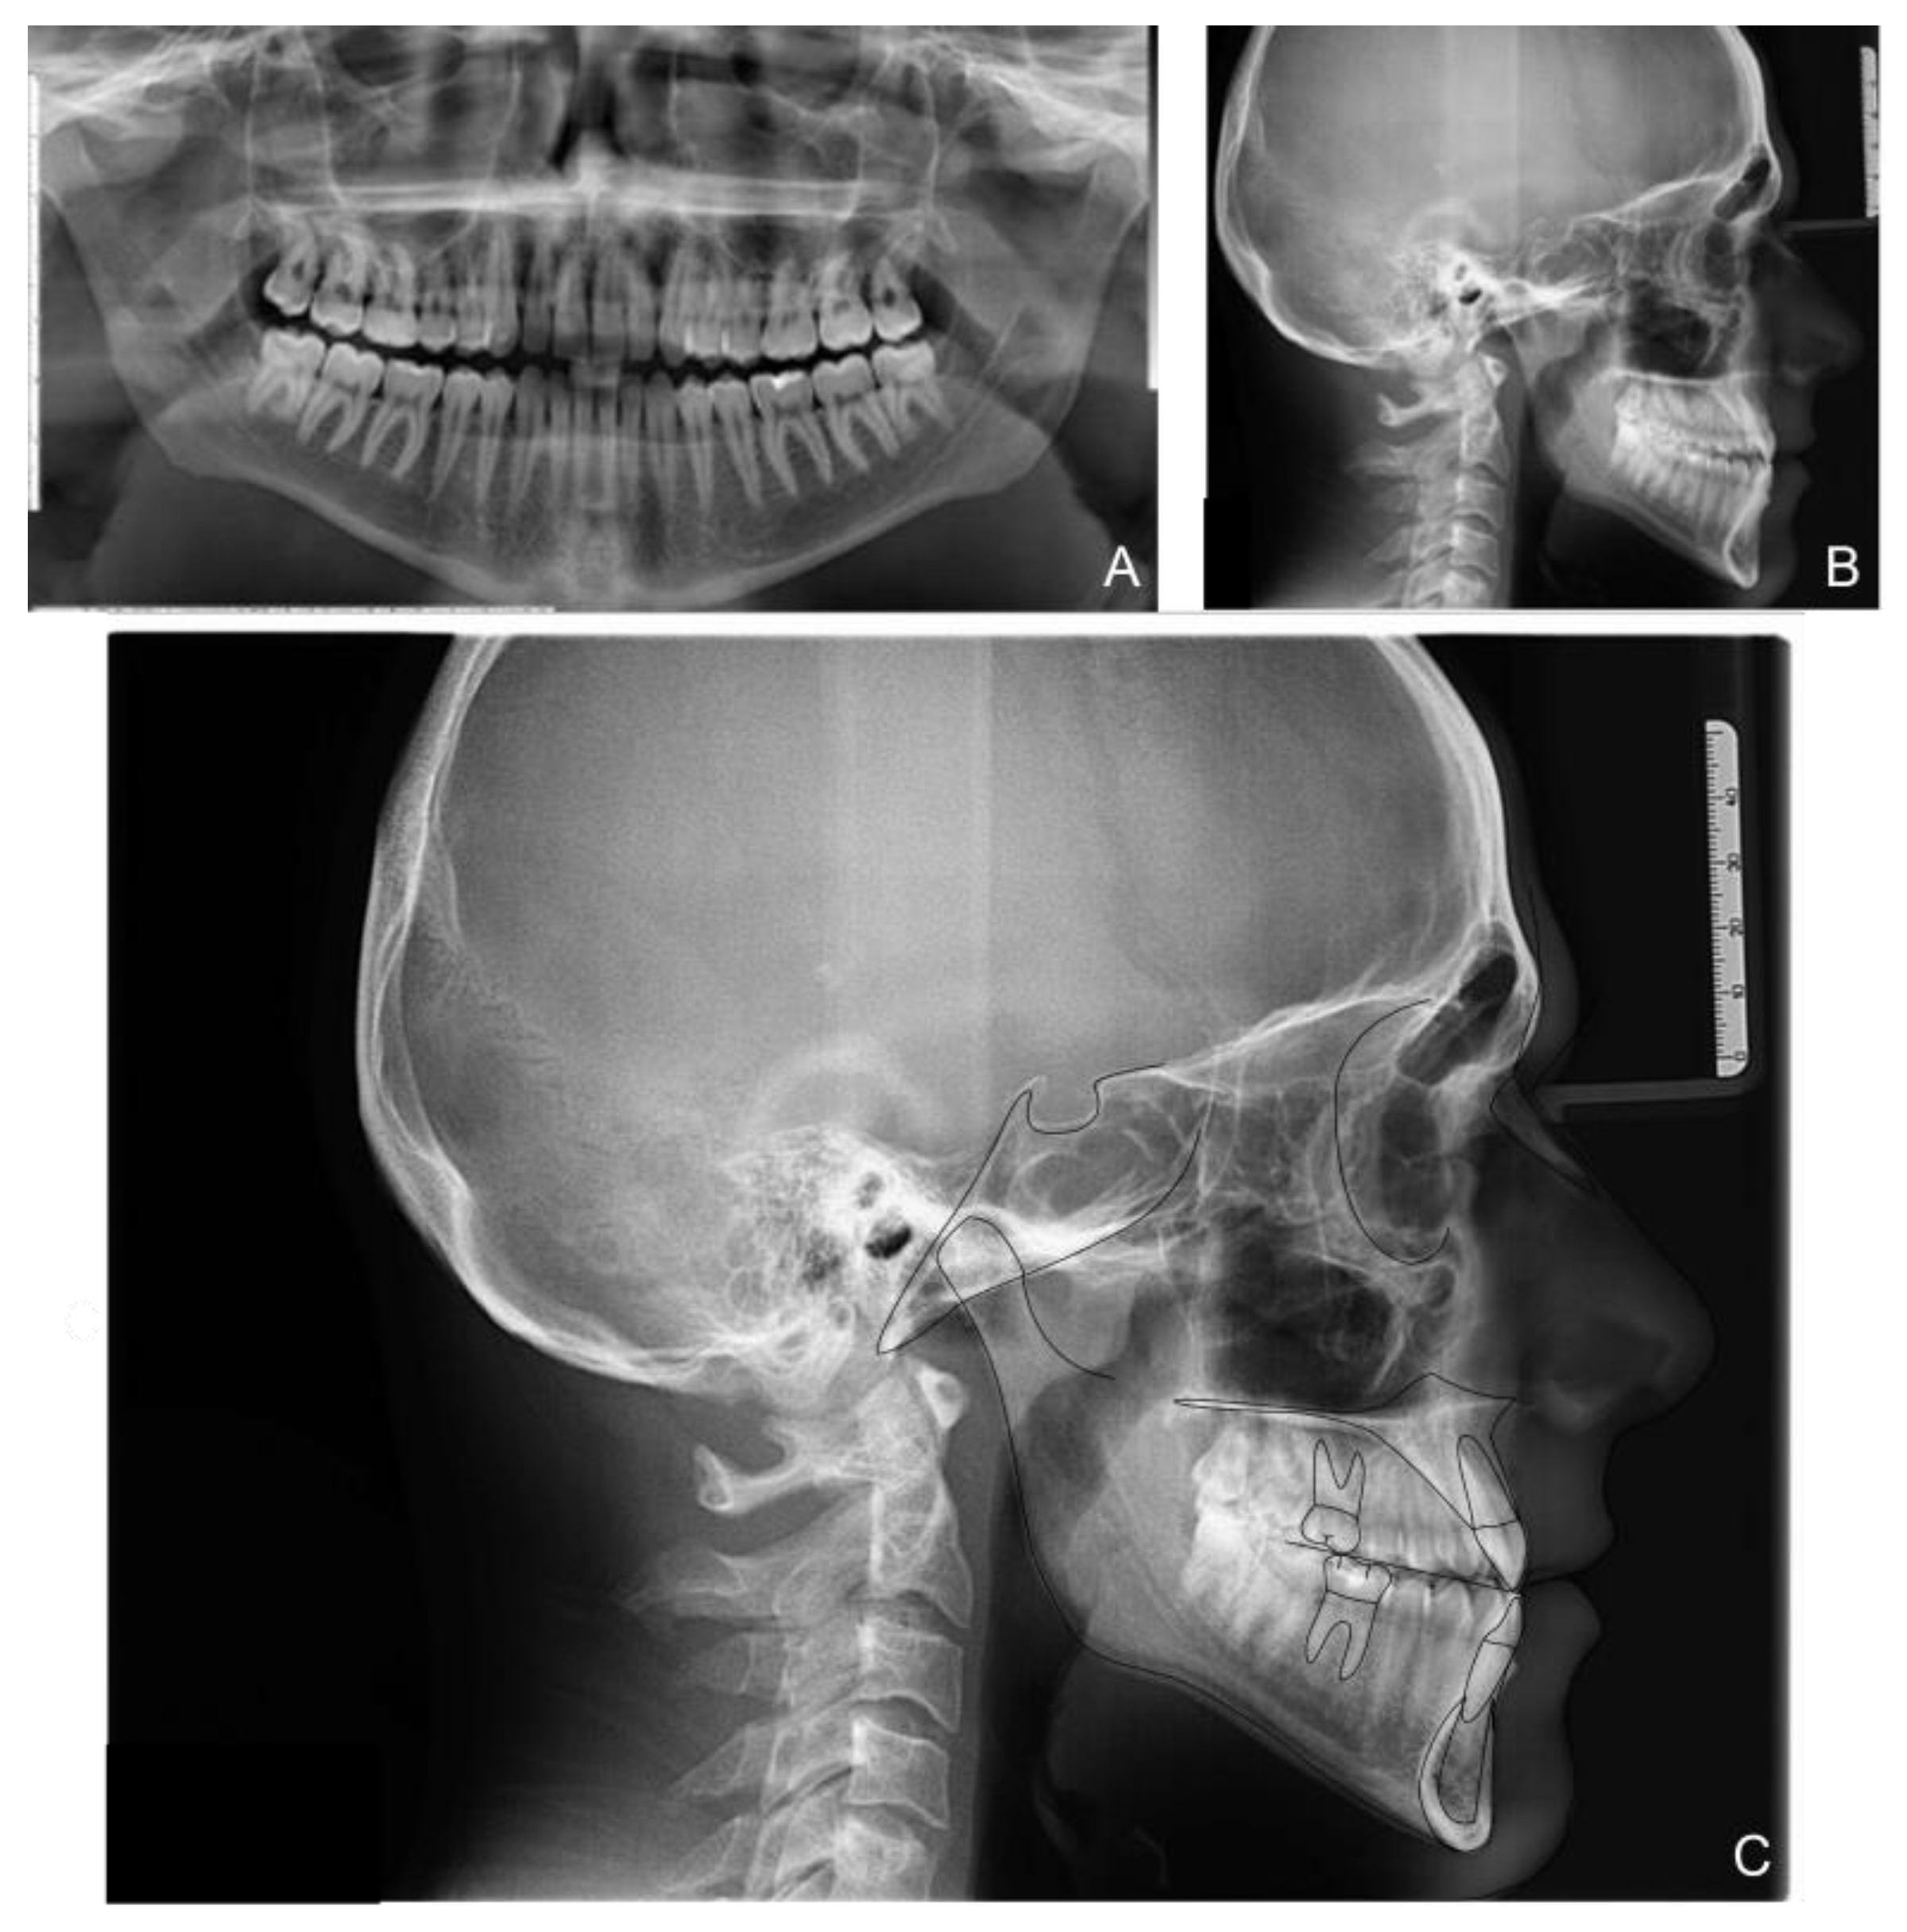

The orthopanoramic X-ray showed the physiological presence of all teeth and their good condition. The latero-lateral skull X-ray revealed a class III hyperdivergent skeletal malocclusion, a slight overbite and a negative overjet. Clinical examination also indicated minor teeth crowding with Angle class III malocclusion and head-to-head incisors relationship (Figure 2 and Table 1).

Figure 2. Patient X-rays, cephalometry tracing and analysis before treatment: panoramic X-ray (A); latero-lateral X-ray of the skull before treatment (B); Cephalometric tracing (C).